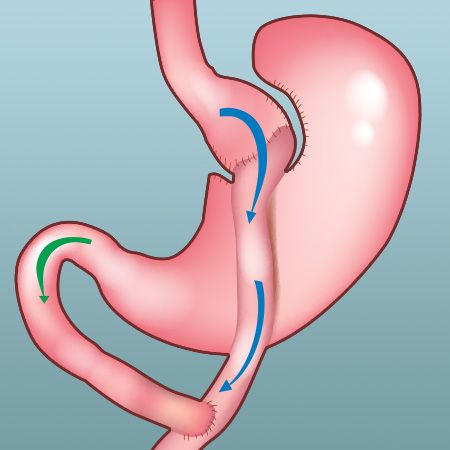

- Gastric Bypass

- Gastric Bypass Surgery

| Gastric Sleeve | $3,999 USD | 4 days 3 nights |

| Gastric Bypass | $4,999 USD | 4 days 3 nights |